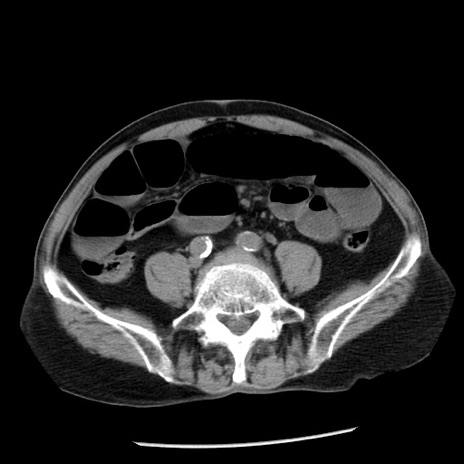

症例26(横断像)

【症例】80歳代男性

【主訴】嘔吐

【現病歴】昨晩2回嘔吐あり、今朝になっても嘔吐あり。来院。

【既往歴】胃潰瘍

【身体所見】意識清明、BT 37.6℃、BP 166/95mmHg、HR 100bpm、SpO2 97%、腹部:平坦・軟、腸蠕動音聴取良好、圧痛なし。

【データ】WBC 21900、CRP 1.46